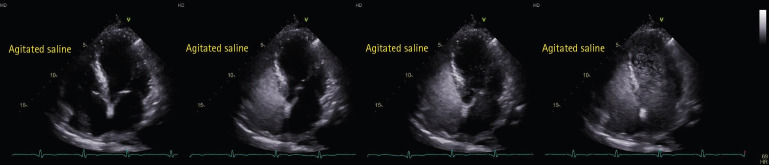

Persistent hypoxemia following myocardial infarction can be challenging to manage and often requires considering uncommon etiologies such as extracardiac shunts. This case report describes a 78-year-old man with persistent hypoxemia post-myocardial infarction, which was ultimately attributed to a large pulmonary arteriovenous malformation (AVM). The patient presented with cardiogenic shock and underwent successful revascularization. Despite clinical improvement, the hypoxemia persisted, prompting further evaluation. Bedside saline contrast echocardiography and computed tomography confirmed the presence of a large pulmonary AVM, explaining the uncorrectable hypoxemia. This case underscores the importance of considering extracardiac shunts in patients with refractory hypoxemia and illustrates the utility of bedside imaging in such situations.